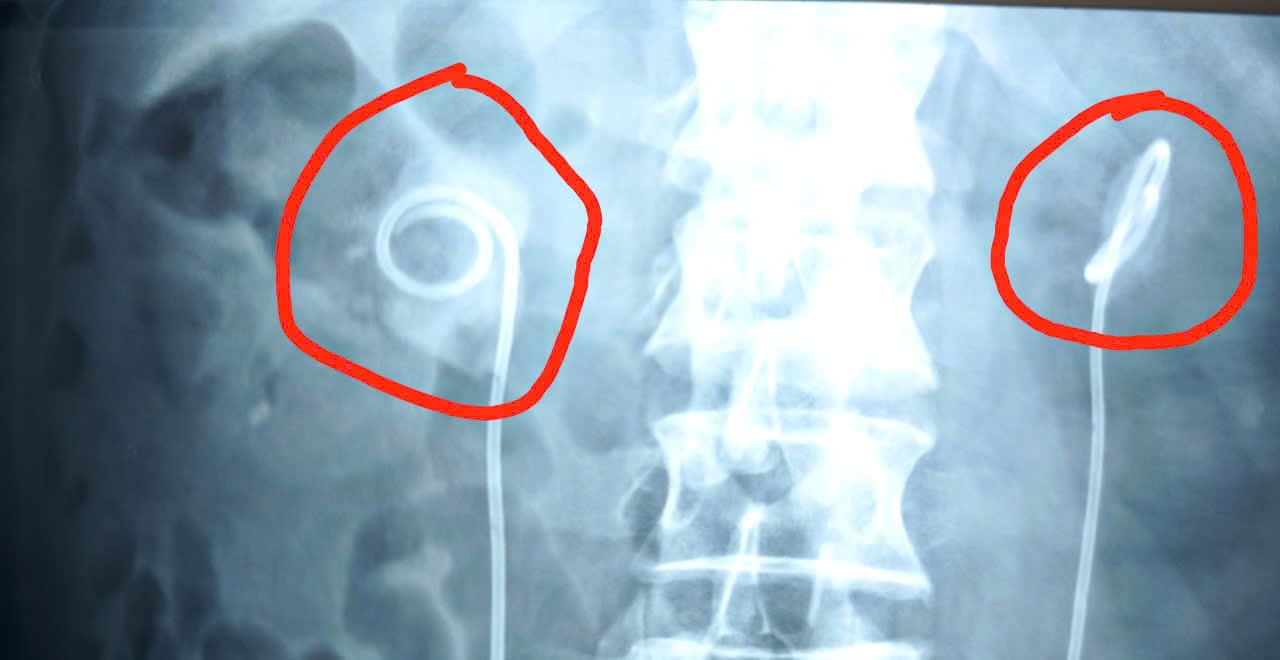

Hình ảnh ống sonde nằm trong cơ thể do bệnh nhân nhất quyết không đi tái khám.

“Qua thăm khám, chúng tôi không thể rút sonde JJ bằng biện pháp thông thường. Do thời gian lưu sonde quá lâu, bệnh nhân được chỉ định chụp CT. Kết quả cho thấy sỏi bám vòng quanh sonde JJ chiếm gần như hết diện tích đài bể thận 2 bên.

Thận phải có viên sỏi lớn 34x29mm, thận trái 20x13mm kèm nhiều viên nhỏ rải rác. Sỏi ở trên thận gây ứ nước thận độ 3. Đặc biệt, chỉ số Kali trong máu của bệnh nhân lên đến 6.9 mmol/L (bình thường Kali máu từ 3.5 mmol/L -5.0 mmol/L), có nguy cơ ngừng tim bất cứ lúc nào.